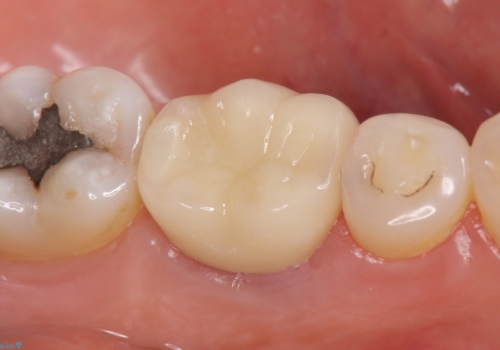

再根管治療終了後、オールセラミッククラウンにて補綴を行いました。

今回用いたオールセラミッククラウンはジルコニアフレームという白い素材の上にセラミックを盛っているため、審美性が非常に高いのが特徴です。

また、ジルコニアは人工ダイヤモンドの材料にも使われているほど高い強度を持っており、そのためオールセラミッククラウンは審美性だけでなく、奥歯やブリッジの補綴も可能とするクラウンです。